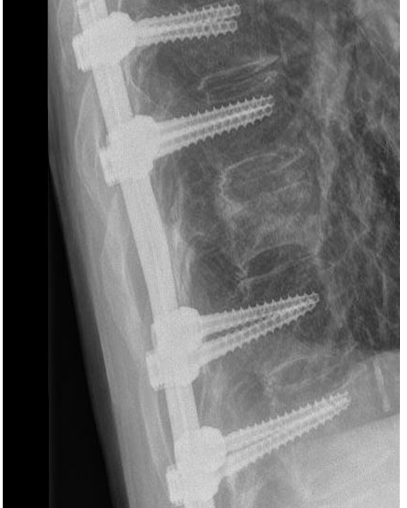

Bij een instabiele breuk is dit risico wel aanwezig en daarom is een stabiliserende operatie noodzakelijk. De revalidatie zal grotendeels overeenkomen met de revalidatie na een stabiele breuk zonder operatie.